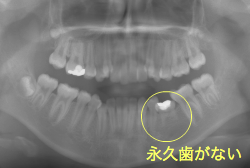

「左奥歯でものが噛めない」という主訴で来院したケースです。診断の結果、基本的には「叢生」という隙間が足りないと言うことが原因の凸凹症例でしたが、左下の乳歯が高校生になってもまだ残存している状態で、そのせいで噛み合わせが極端に悪くなっていました。

検査の結果、乳歯の下には後継ぎの永久歯が先天的に欠如していました。配列の凸凹が厳しく非抜歯で矯正することは難しく、仮に無理をして非抜歯治療をしても後々「後戻り」が懸念されることから、このような症例の場合は通常、上下顎左右第一小臼歯を抜歯させていただくのですが、左下は乳歯を抜歯して、第一小臼歯は残すことにしました。これで結果として、小臼歯部を上下左右で一つずつ減らしたのと同じ状況になります。治療後は歯並びが綺麗になっただけでなく、噛み合わせ的にも正しい状態が確立しています。

このように、先天的に永久歯が足りないという症例は最近増えています。親知らずはなくても特に問題になりませんが、その他の歯が足りないと言うのは審美的にも機能的にも重大な障害となります。しかし、矯正治療を正しく行えば、結果として歯がすべてあった場合と全く同じ仕上げにすることも可能です。